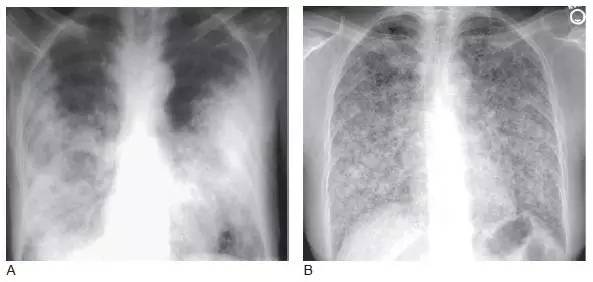

图9 弥漫性细支气管肺泡癌(BAC)

A. 伴双肺实变的BAC;

B. 伴两肺模糊小结节;

C. 同一患者高分辨率CT 显示弥漫分布的小结节